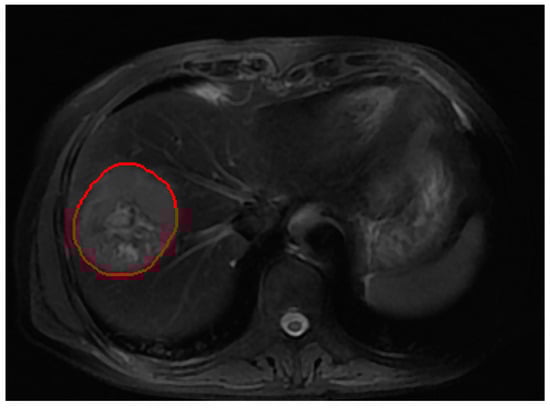

2.3. Image Acquisition and Tumor Segmentation